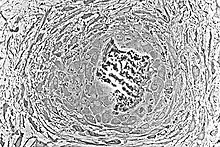

Formación de osteonas

Las osteonas son las unidades o estructuras principales del hueso compacto. Durante la formación de espículas óseas, los citoplasmas de los osteoblastos se interconectan, convirtiéndose en los canalículos de las osteonas. Como las espículas óseas tienden a formarse alrededor de los vasos sanguíneos, el espacio perivascular se reduce drásticamente, ya que el hueso sigue creciendo. Cuando se produce el reemplazo de hueso compacto, este vaso sanguíneo se convierte en el canal central de las osteonas.